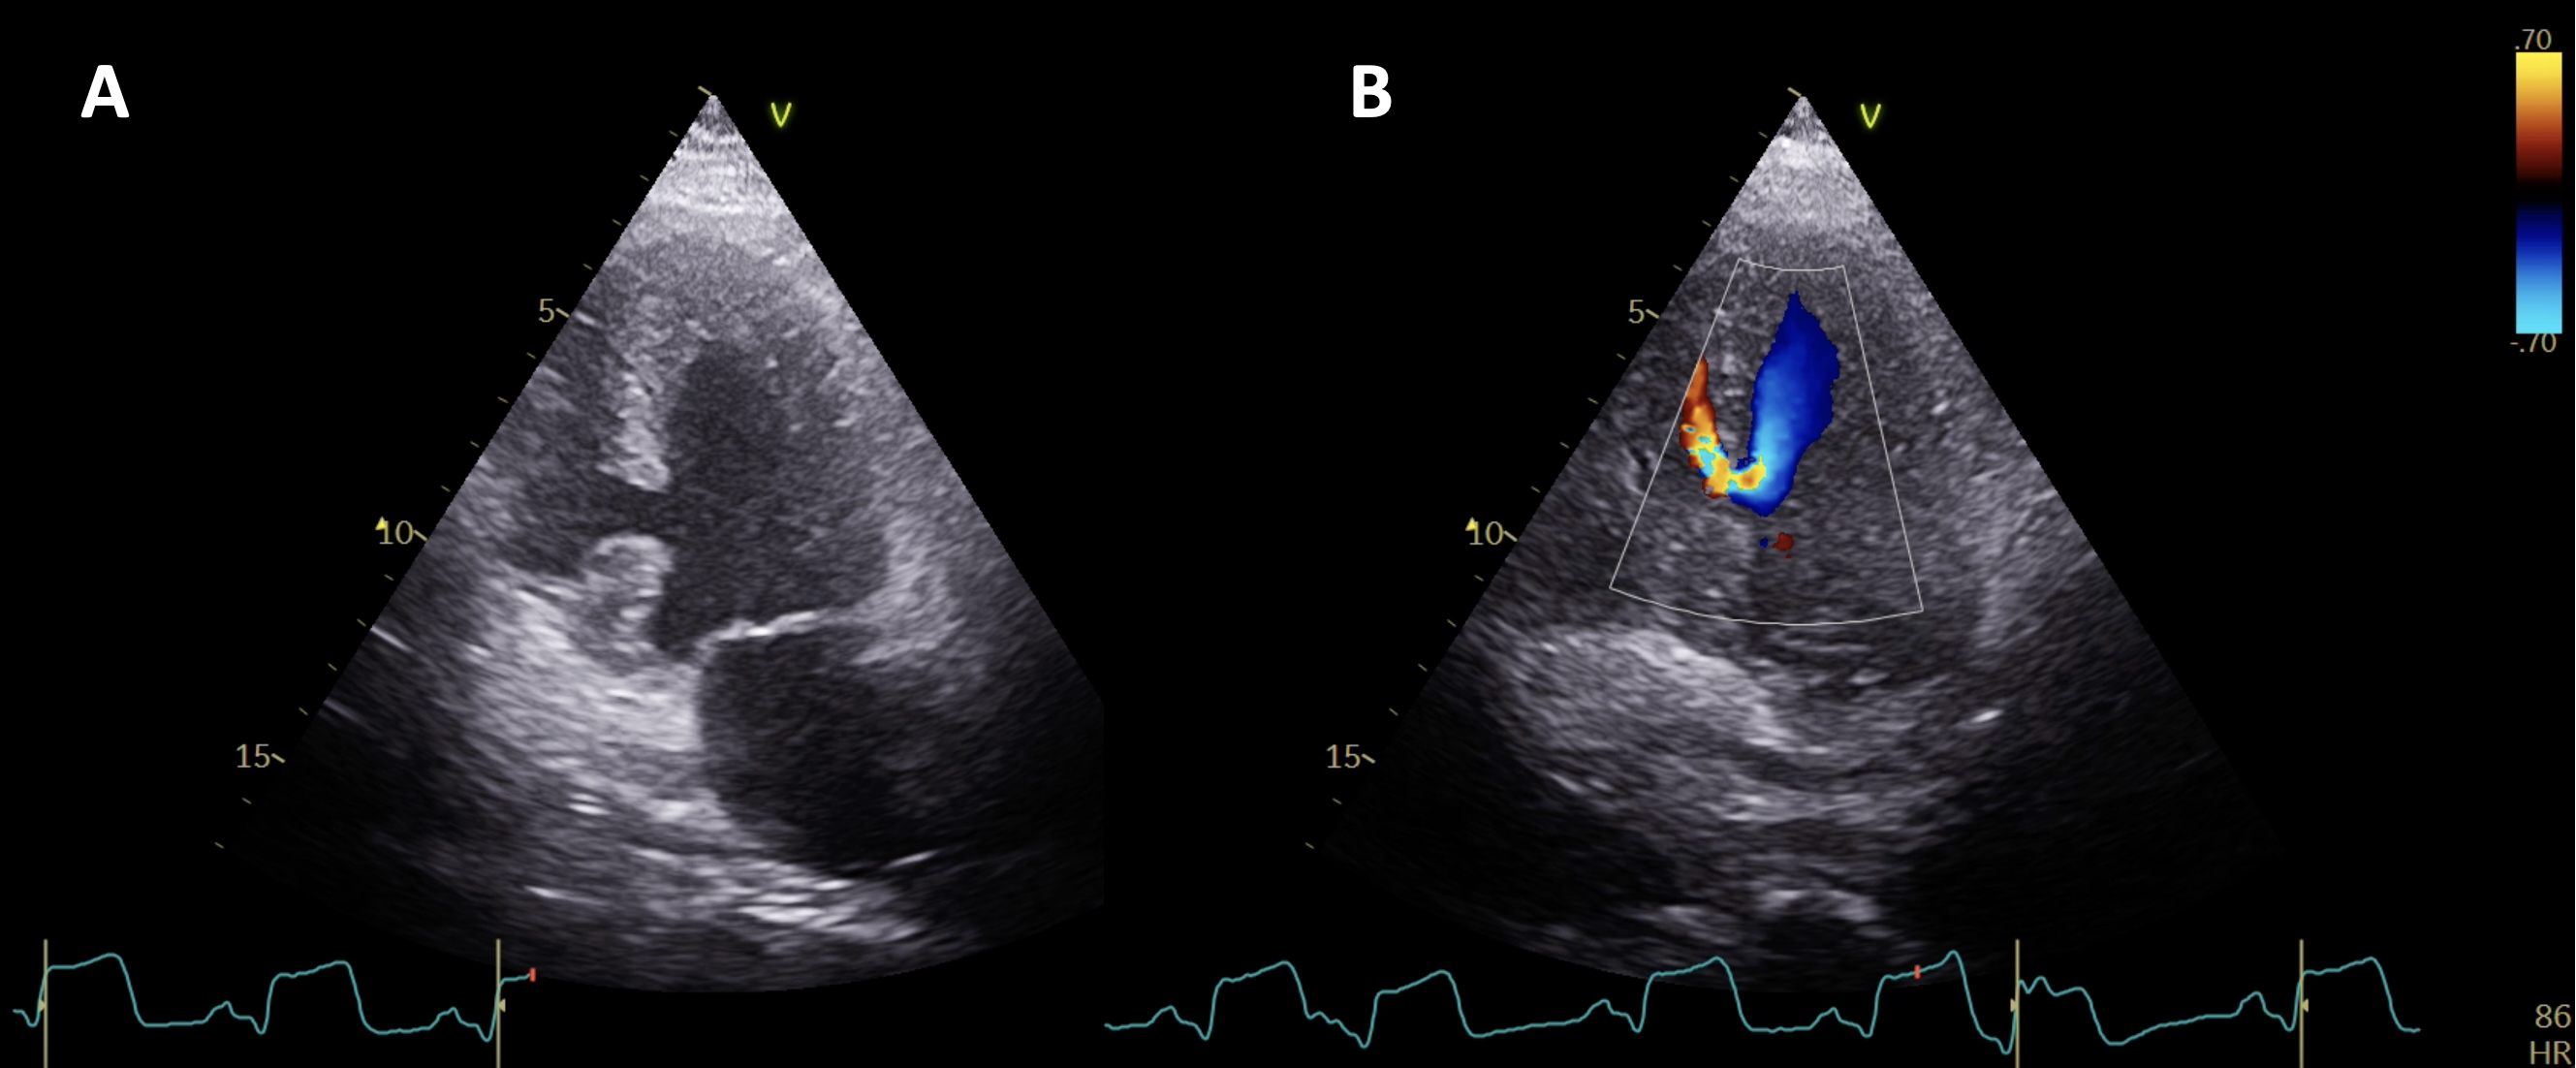

Within 30 minutes, the patient demonstrated rapid deterioration, with a significant drop in arterial BP accompanied by a new onset holosystolic murmur over the precordium, along with a gallop rhythm. Bedside transthoracic echocardiography revealed thickened walls in the left ventricle and an 11-mm-wide ventricular septal rupture with dissection at the junction of the basal inferoseptum and mid-inferoseptum segments (Figure, Videos 1 and 2). Vasopressor support with norepinephrine was initiated. Coronary angiography demonstrated a 100% occlusion at the mid-right coronary artery with the presence of an established thrombus, and no critical stenoses were seen in the left coronary system (Video 3). Subsequently, an intra-aortic balloon pump was placed because of severe hemodynamic instability. The patient was transferred to the closest cardiac surgery center for emergency surgical repair of the ventricular septal rupture; however, the patient died a few hours after the surgical procedure.